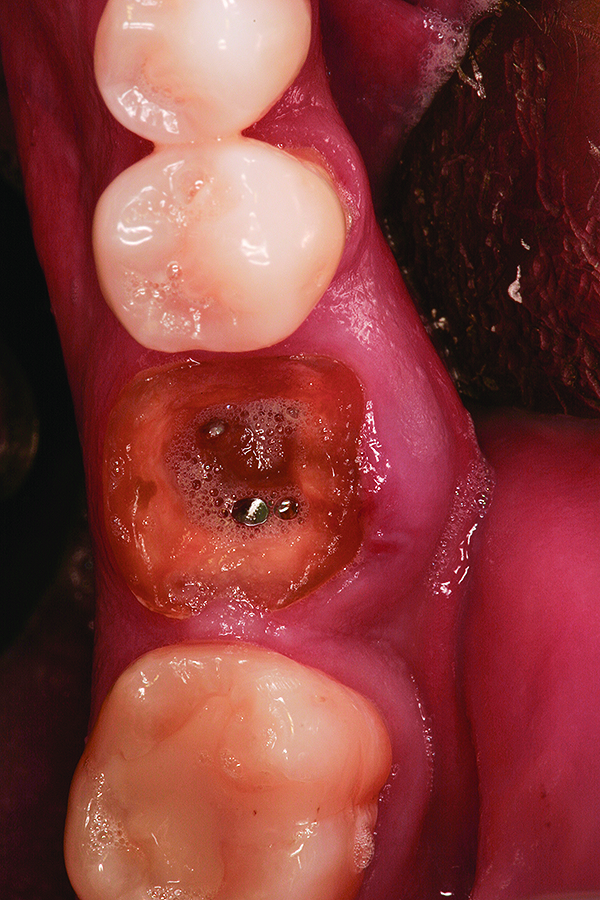

Fig 9. Note the significant osseous defect in the buccal osseous wall following atraumatic tooth extraction.

Figure 9